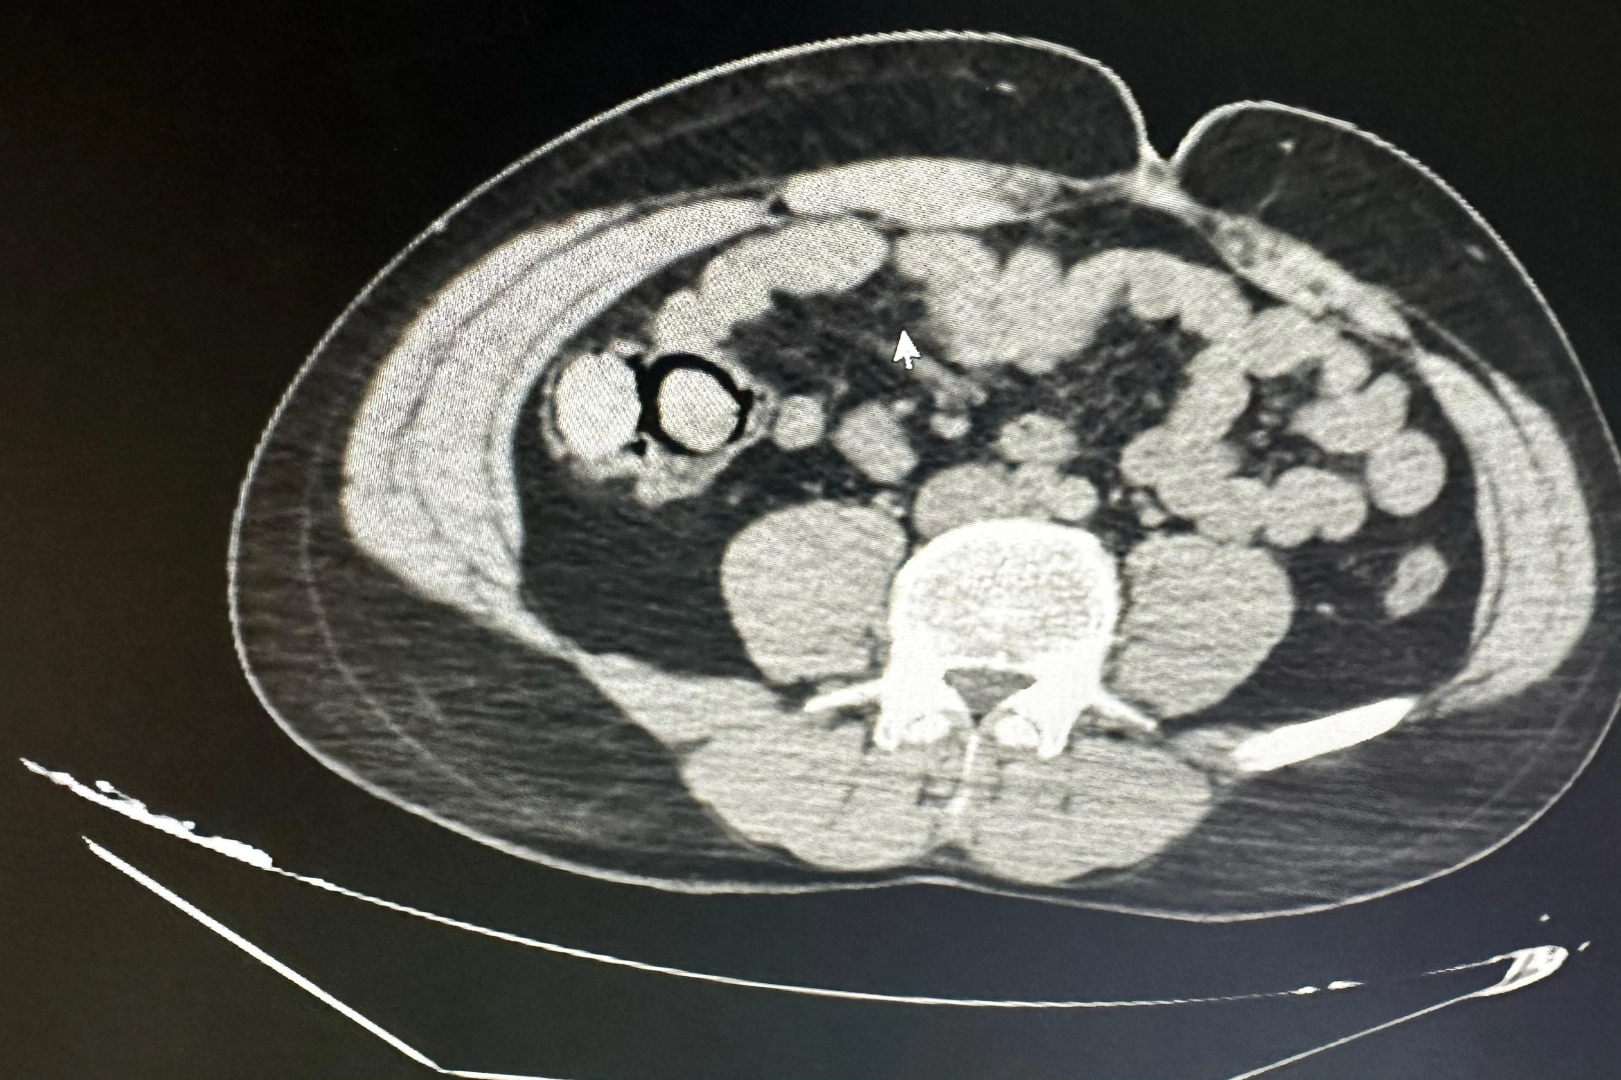

Otobüs yolculuğu sırasında polis ekiplerince durdurulan yabancı uyruklu iki şahsın midesinden 10 parça halinde 113 gram metamfetamin çıktı. Bingöl Emniyet Müdürlüğü Narkotik Suçlarla Mücadele Şube Müdürlüğüne bağlı narko-timleri akıllara durgunluk veren bir uyuşturucu kaçakçılığını çözdü.

Ekiplerin çalışmaları neticesinde otobüs ile Bingöl’e gelen şüpheli yabancı uyruklu 2 şahsın iç beden muayenesinde 10 parça halinde 113 gram metamfetamin maddesi tespit edildi. Emniyetteki işlemlerinin ardından mahkemeye çıkarılan 2 şahıs, uyuşturucu madde ticareti yapmak suçundan tutuklanarak Elazığ Kapalı ceza infaz kurumuna teslim edildi.